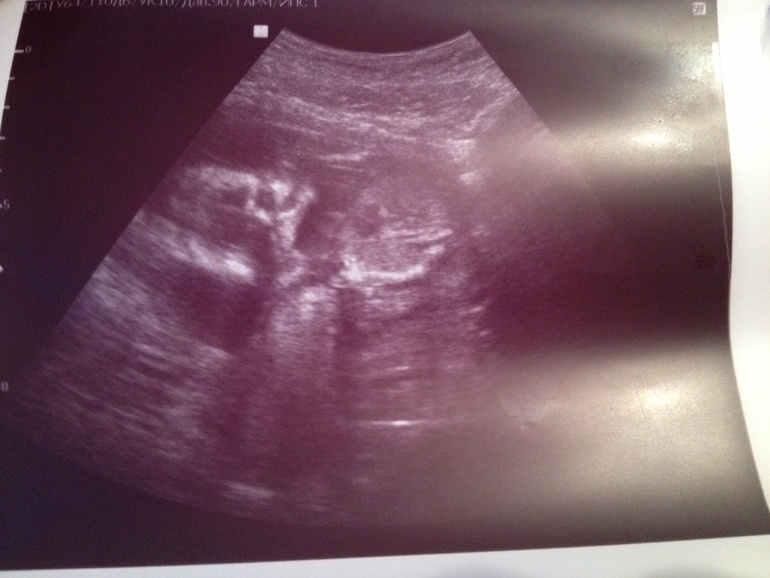

Алина 11 лет Доченька!!! Растем здоровые и длинные) Врач говорит, что родиться будущая модель) Мы очень ждем тебя, Маруся! Посмотрите еще 20 записей на эту тему Отменить Ответить Узи! Первые шевеления! Чаты Беременных Выберите чат: Январята-2026 Февралята-2026 Мартята-2026 Апрелята-2026 Майчата-2026 Июнята-2026 Июлята-2026 Августята-2026